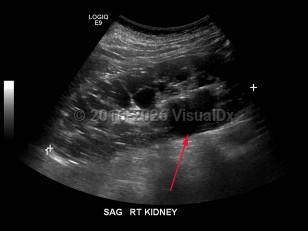

Hydronephrosis